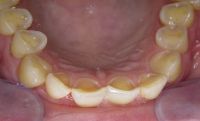

Voor de behandeling

Gebitsslijtage voornamelijk door knarsen. Aan de binnenkant zijn de tanden erg dun geworden en daardoor ook afgebroken. Door de diepe beet zijn de kiezen in onderkaak helemaal afgebroken.

Na de behandeling

De zes voortanden en twee kleine kiezen in de bovenkaak zijn opgebouwd met composiet. Hierdoor zijn ze verlengd en volledig ingepakt met composiet, zodat ze niet meer zo snel kunnen breken.

De afgebroken kies in de onderkaak is verwijderd en in het hiaat zijn twee implantaten geplaatst met kronen.

Uiteindelijk heeft meneer ook een beschermende nightguard gekregen om ervoor te zorgen dat het knarsen geen schade kan geven aan zijn gebit.